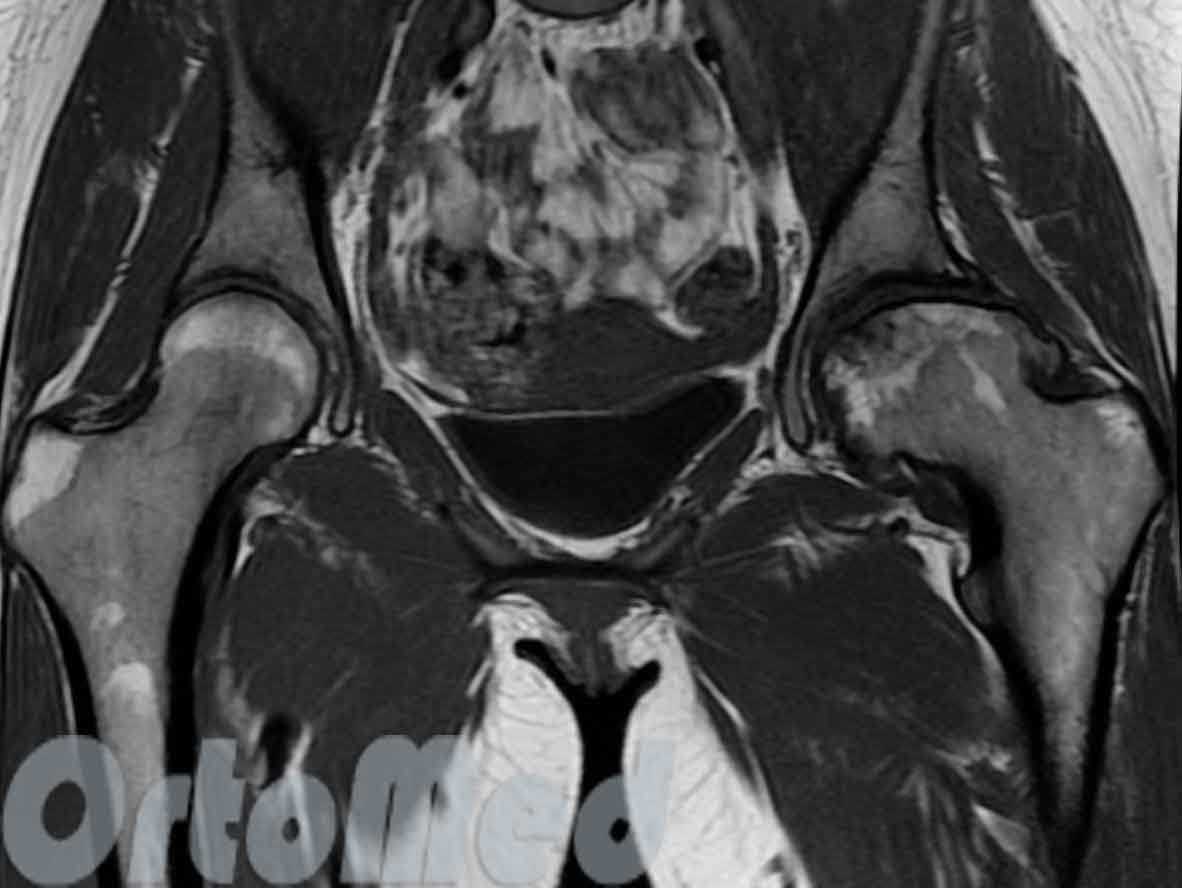

Асептический некроз головки бедренной кости (аваскулярный некроз или остеонекроз). Вследствие разных причин нарушается питание участка костной ткани и хряща головки бедренной кости, хрящ «сминается» или «отслаивается» с дальнейшим развитием патологического процесса.

Асептический некроз головки левой бедренной кости

На магнитно-резонансной томографии четко виден очаг разрушения в нагружаемой части головки левой бедренной кости